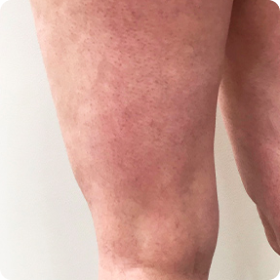

Ahora me arrepiento de haber gastado tanto dinero y tiempo en ir al especialista. Ojalá hubiera probado esta crema de inmediato. Era mucho mejor que el láser. En primer lugar, las venas desaparecieron.

Han desaparecido por completo. La piel de mis piernas es uniforme y de color normal. En segundo lugar, ya pasaron seis meses y mis piernas siguen limpias: ¡no hay vasos, ni el más pequeño!